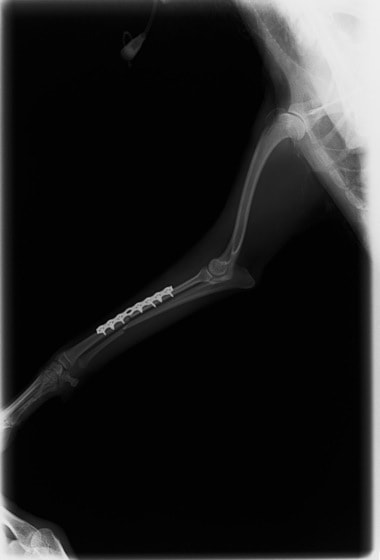

他院にて左大腿骨遠位の成長板骨折(salter-harrisⅠ型)が認められており、治療相談を目的として来院。当院にて、キルシュナーワイヤーを用いたピンニングにより骨折部位の整復を行いました。術後の経過は良好で、現在も経過観察中です。

術後レントゲン

Arthrex社のターゲティングデバイスを用いてピンニングの位置を調整することで、確実な固定を行っています。当院ではこの手術器具以外にも、人の手術にも使用される様々な器具を導入し、手術精度を高め、また医療メーカーと新しい器具の開発、試作にも取り組んでおります。